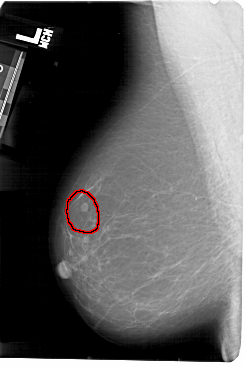

A_1476_1.LEFT_MLO

LEFT_MLO LINES 5491 PIXELS_PER_LINE 3676 BITS_PER_PIXEL 12 RESOLUTION 43.5 OVERLAY

FILE: A_1476_1.LEFT_MLO.OVERLAY

TOTAL_ABNORMALITIES 1

ABNORMALITY 1

LESION_TYPE MASS SHAPE ROUND MARGINS CIRCUMSCRIBED

ASSESSMENT 4

SUBTLETY 4

PATHOLOGY BENIGN

TOTAL_OUTLINES 1

BOUNDARY